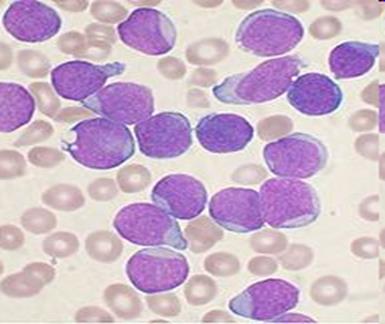

La leucémie (du grec leukos, blanc, et haima, sang), ou leucose, est un cancer des cellules de la moelle osseuse. En 1847, Rudolf Virchow, un médecin histologiste allemand, fut l'un des premiers à décrire la leucémie.